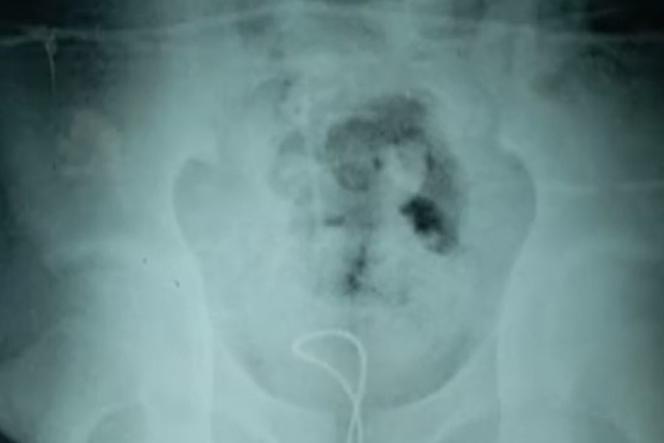

Jakim cudem ten przedmiot mógł znaleźć się w tym miejscu?! Odpowiedź na to pytanie z pewnością zna jedynie 13-letni chłopiec, który włożył sobie ładowarkę do... penisa. Poszkodowany pacjent został zawieziony do szpitala przez rodziców, a lekarze mieli przed sobą nie lada wyzwanie. Po przejrzeniu zdjęć rentgena okazało się, że kabel związał się na supeł. Kiedy lekarzom nie udało się wyciągnąć ładowarki po nasmarowaniu penisa specjalnym środkiem, postanowili usunąć przedmiot chirurgicznie. 13-latek opuścił szpital 3 lipca.